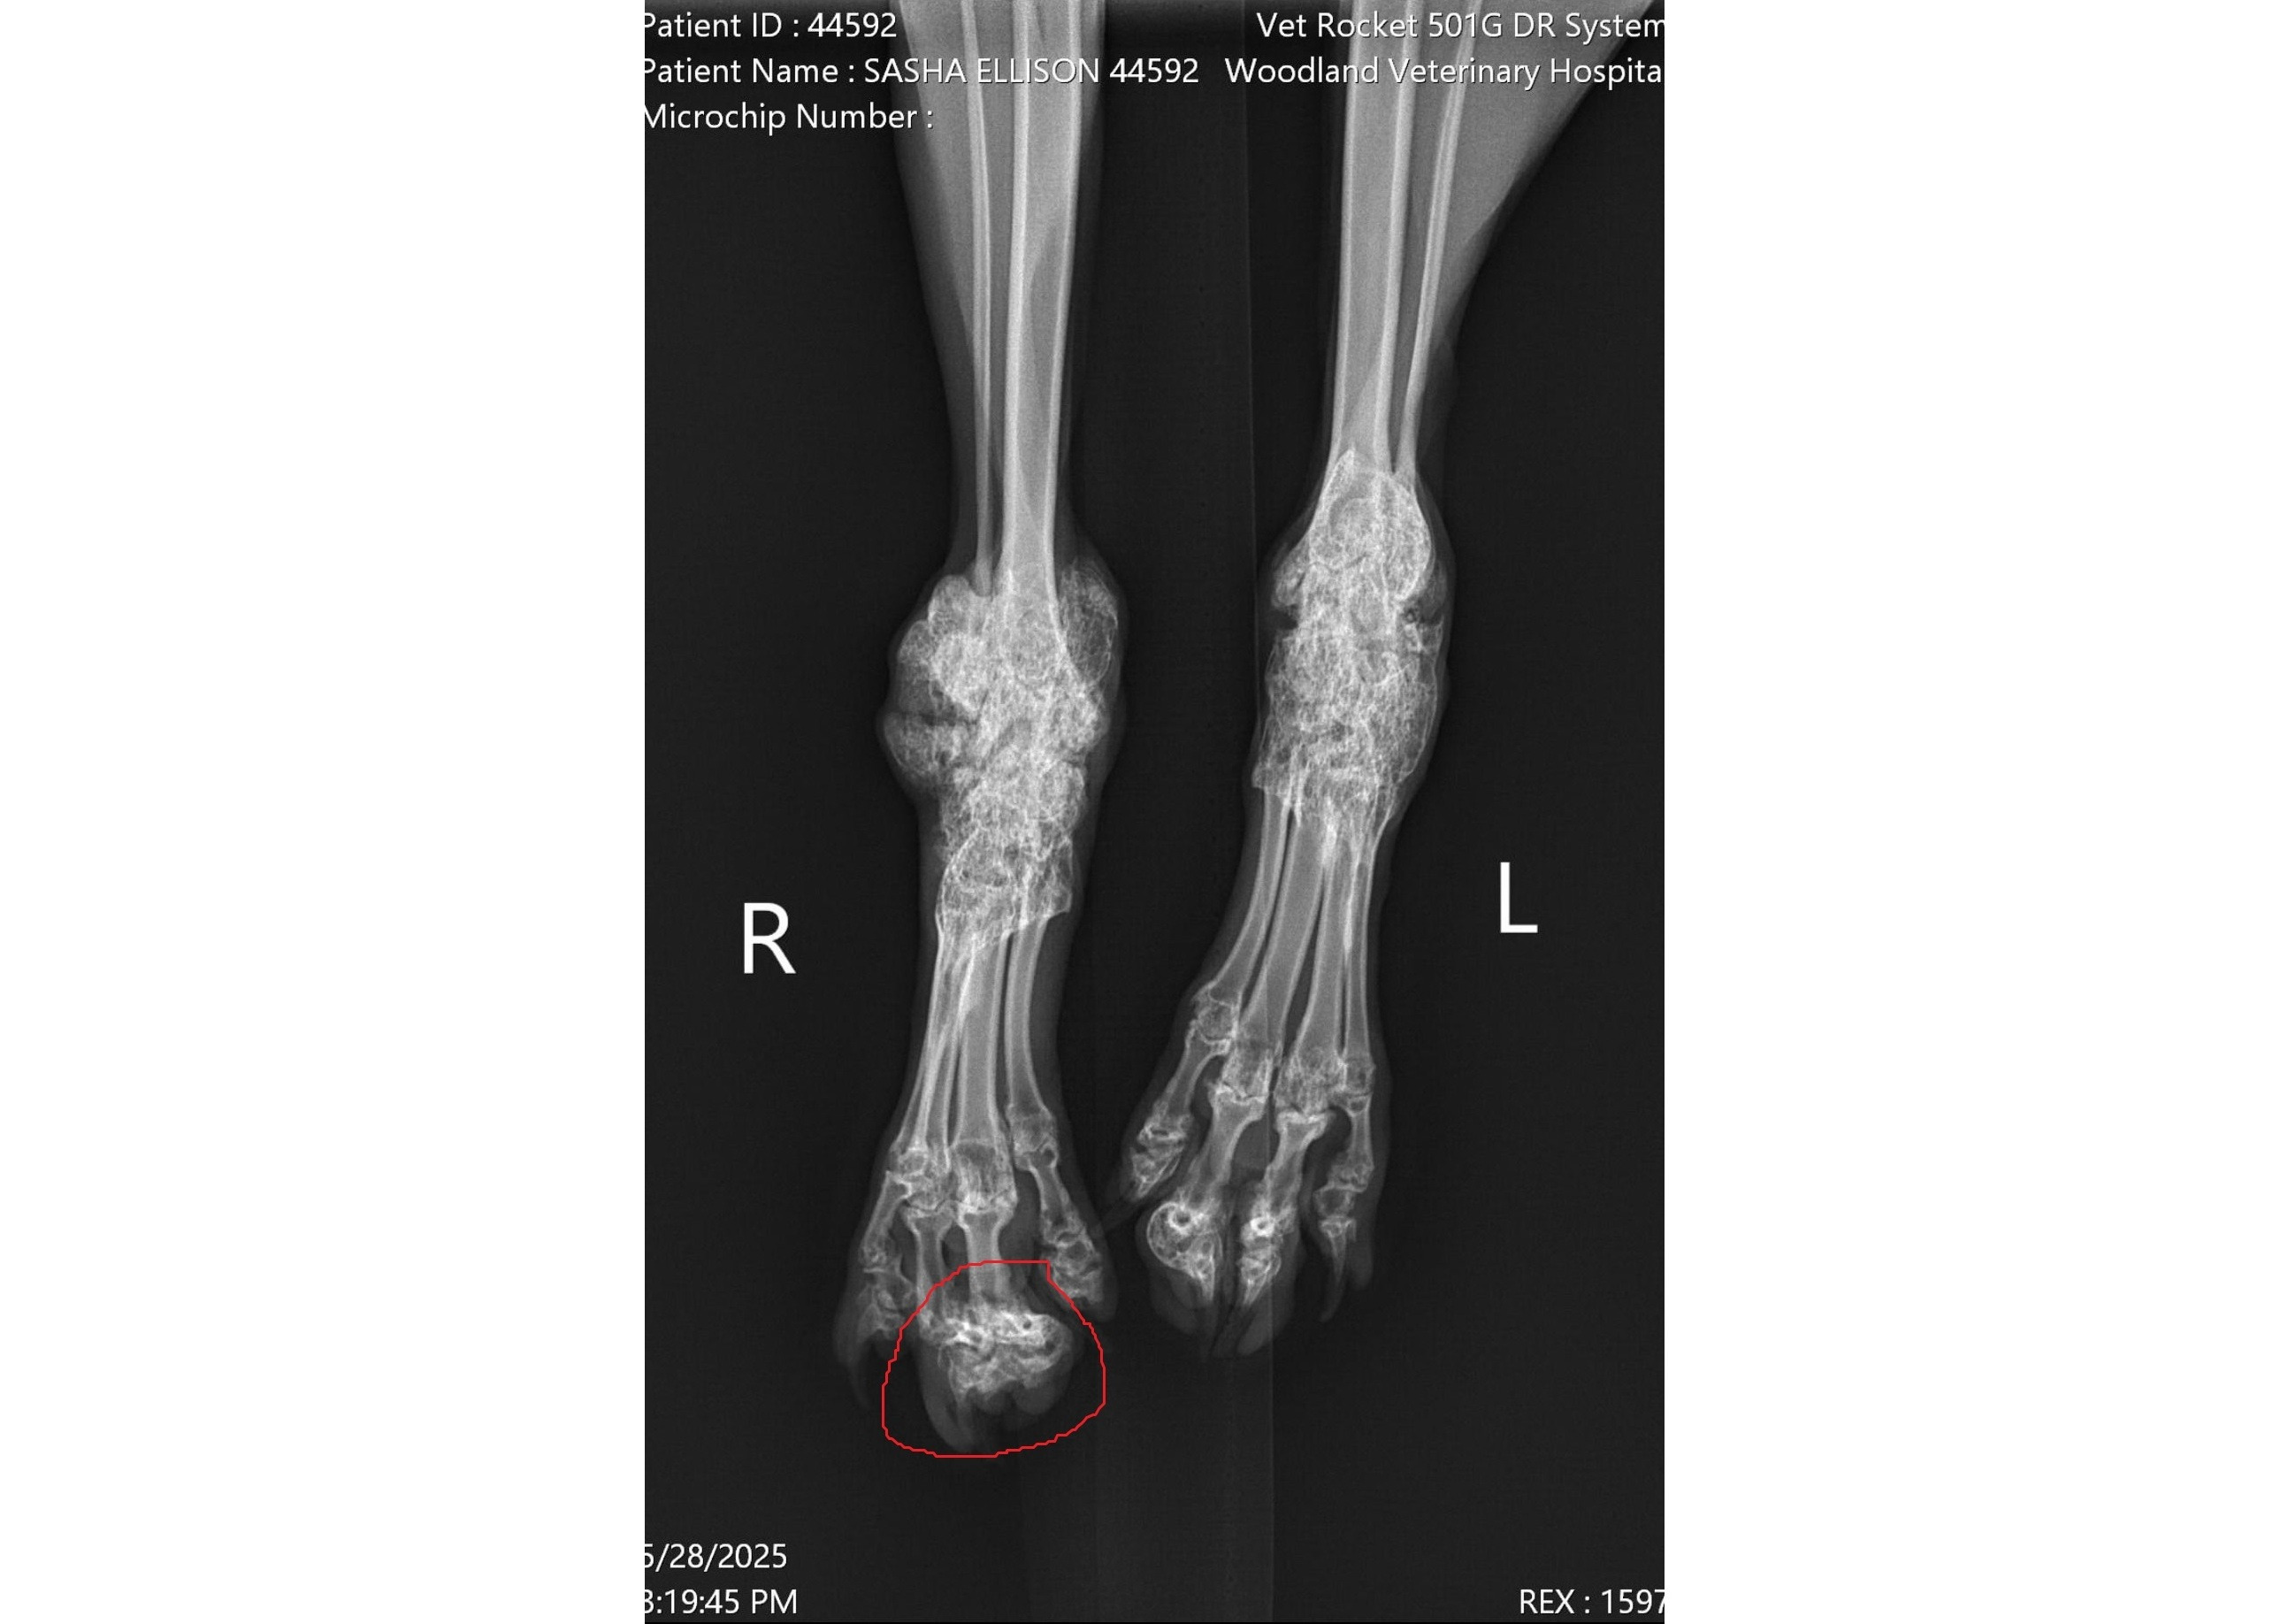

Unfortunately, Sasha was born with a genetic condition known as Scottish Fold Osteochondrodysplasia, or Scottish Fold disease. While this mutation gives Scottish Folds their distinctive and adorable folded ears, it also leads to painful and debilitating bone disease. Over time, Sasha has developed significant bone growth around the joints in her hind legs, including her ankles and toes. This has caused her considerable discomfort and has now progressed to the point where one of her toes is so swollen with bone that she can no longer walk on it. Although this condition cannot be cured, surgery could greatly improve her quality of life: Sasha now requires a single digit amputation to relieve her pain and help her regain mobility. Due to her rare and complicated condition, this surgery requires specialist care and is incredibly costly. The estimate for this procedure and post-operative care lies between $5,000 to $6,000.